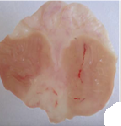

Oral administration of aqueous and methanol extracts of D. thollonii at the dose of 500 mg/kg for 14 consecutive days of treatment significantly (p<0.01) decreased the area of chronic ulcer induced by acetic acid compared with the negative control group treated with distilled water. The total surface area of 29.0±2.3 mm2in the negative control was significantly (p<0.01) reduced to 18.2±0.9 and 14.5±1.6 mm2in animals which received aqueous and methanol extracts (table 3 and fig. 3). Maalox (50 mg/kg) speeded up the healing of gastric ulcer, reducing the area of the lesion to a statistically significant (p<0.01) extent by 19.2±1.8 mm2 (33.7 %) compared to the negative control group (29.0±2.3 mm2). There were no visible signs of toxicity (change in behavior or locomotory activities, or diarrhea) in animal receiving drug (extracts, Ranitidine or Maalox) for 14 days.

Fig. 3: Macroscopic study of acetic acid-induced gastric damage in rats

In fig. 3, (a): stomach of a normal control rat: no injuries to the gastric mucosa are seen and the gastric wall is normal. (b): stomach of an ulcer control rat: there is severe destruction of the surface epithelium and necrotic lesions penetrating deeply into mucosa and submucosa layers. (c): stomach of rat treated with Maalox (50 mg/kg): the gastric wall appears normally, but sometime there is edema of submucosa layer. (d): stomach of rat treated with Ranitidine (50 mg/kg): the gastric wall appears normally with all layers. (e): stomach of rat treated with 125 mg/kg of aqueous extract: there is mild disruption of the sub mucosal layer. (f): stomach of rat treated with 250 mg/kg aqueous extract: there is moderate disruption to the surface epithelium. (g): stomach of rat treated with 500 mg/kg of aqueous extract: there is mild disruption of sub mucosal layer and edema of the muscle. (h): stomach of rat treated with 125 mg/kg of methanol extract: there is mild disruption to the epithelium surface and the sub mucosal layer and edema of the serosal layer. (i): stomach of rat treated with 250 mg/kg of methanol extract: there is mild disruption to the epithelium surface. (j): stomach of rat treated with 500 mg/kg of methanol extract: there is moderate disruption of the epithelium surface although the gastric wall appears normally.